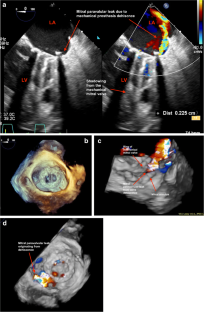

Fig. 2